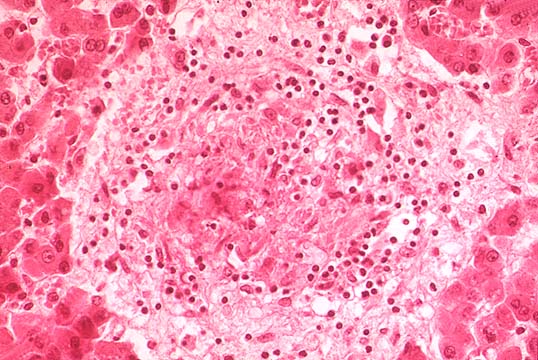

TB granuloma

Fig.136-TB granuloma

,early, in the middle of the lobule. On the part of the liver there is only moderate, non-specific portal inflammation and some compression of the liver plates.(H&E stain)

Same TB granuloma

Fig.137-Same TB granuloma

at higher power containing histiocytes and many neutrophils which are a distinguishing feature from non- infectious granulomas. No giant cells nor caseation necrosis at this early stage.(H&E).